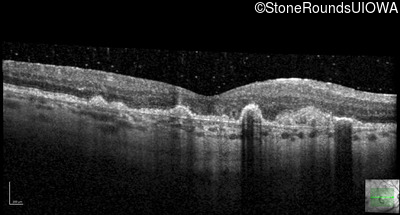

Malattia Leventinese (IIJ)

Malattia Leventinese (IIJ)

This 43 year old woman has experienced a gradual reduction in her central vision for the past 3 years.

| Malattia Leventinese | EFEMP1 | Arg345Trp CGG>TGG | AD |